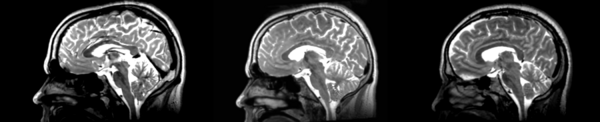

Different subject registration

In this, I'll be moving images like so:

- 01053-t2 -> 01031-t2 = Result. All the images shown have the moving image on the left, the resultant image in the middle, and the target image on the right.

Rigid

01053>01031rigid.png = not bad... different brains of different sizes, but seem to be aligned in the ventricles so output seems okay. output slightly blurry. bad initial leveling displays.

Linear

01053>01031linear.png = not bad... different brains of different sizes, but seem to be aligned in the ventricles so output seems okay.output slightly blurry. bad initial leveling displays.

Affine

01053>01031_affine.png = looks good in terms of size. odd warping of frontal lobe and cerebellum area, but otherwise good coregistration.